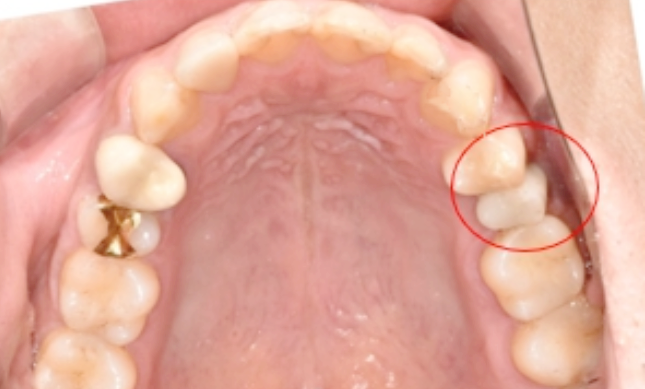

Before (임플란트 전)

먼저 치아 엑스레이를 촬영하였고, 현재 치아의 상태에 대해 살펴보았습니다.

확인해 보니, 좌측 상단의 치아가 딱딱한 음식을 씹으며 치아가 떨어졌지만, 뿌리가 남아있는 상태로, 발치를 먼저 진행해야 하는 상황이었습니다.